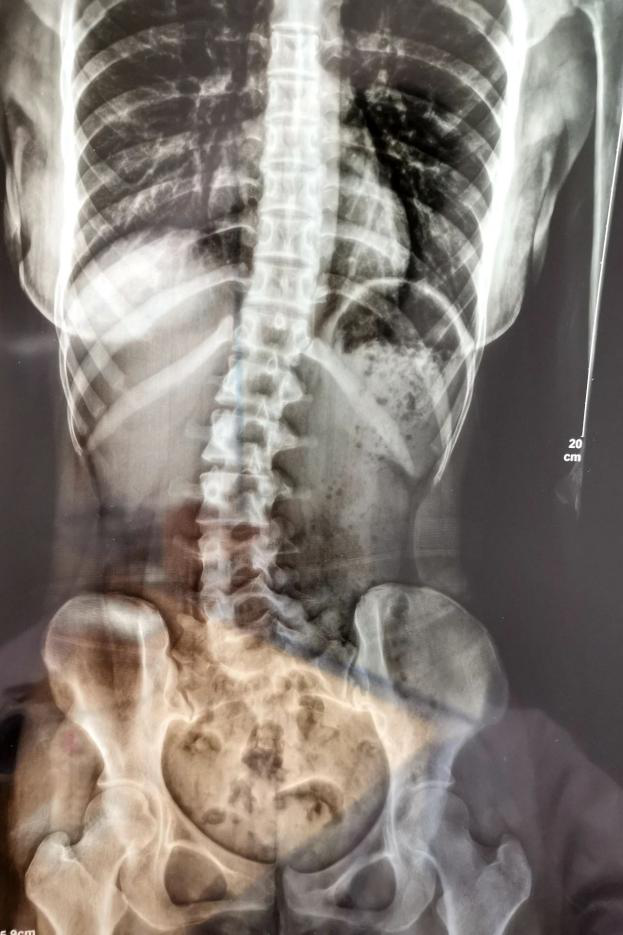

18岁的小邹,在学习久坐后会常常出现腰痛,脖子伏案久了会有一点酸,近期酸痛情况逐渐严重,遂来到广医三院中医科就诊。经过x光检查发现其腰椎向右侧弯、旋转,并以腰2椎体为中心向右侧弯,Cobb角约10°,脊柱向右发生明显侧弯。

△小邹的脊柱明显侧弯。图源:信息时报(由医院提供)